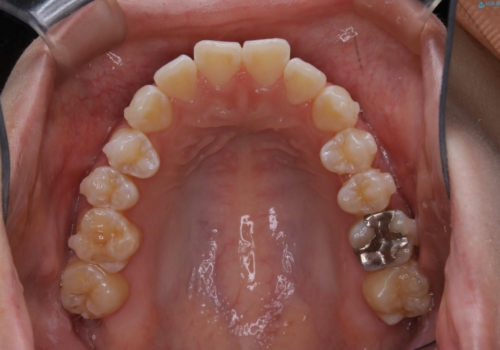

前歯で噛めない:オープンバイト(開咬)を非抜歯インビザラインで治療

- 上下の歯が噛んでいないことを気にしてご相談にいらした方です。

オープンバイトの方への治療は、通常抜歯を行いワイヤーによる矯正治療を行うことが多いですが、今回はインビザラインの特性を生かし、非抜歯にて綺麗な歯並びを作ることが出来ました。

舌癖がある方は、歯を内側から押し出す力が日常的に働くため、矯正治療後も歯と歯の隙間が開いてしまうなどの後戻りのリスクが高いことが知られています。舌の正しいポジショニングやお口周りの筋肉のトレーニングを行うことで後戻りのリスクを減らすことが可能です。